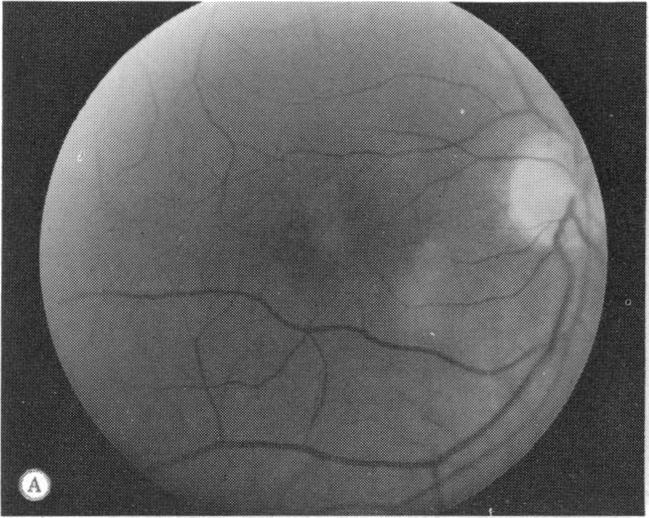

A family with a unique hereditary macular dystrophy is presented. The disorder is transmitted as an autosomal dominant trait having high penetrance and variable expression. The characteristics of this dystrophy are: childhood onset; nonprogressive areolar depigmentation of the central macula; and with the exception of one eye with a macular hemorrhage, normal vision acuity and retinal-function studies.

本文报告了一个患有独特遗传性黄斑营养不良的家族。该疾病以常染色体显性性状遗传,具有高外显率和可变表达。这种营养不良的特征为:儿童期发病;中央黄斑区出现非进行性乳晕色素脱失;除一只眼睛有黄斑出血外,视力和视网膜功能检查正常。